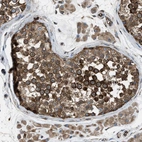

Immunohistochemical staining of human testis shows strong cytoplasmic positivity in cells of seminiferus ducts.